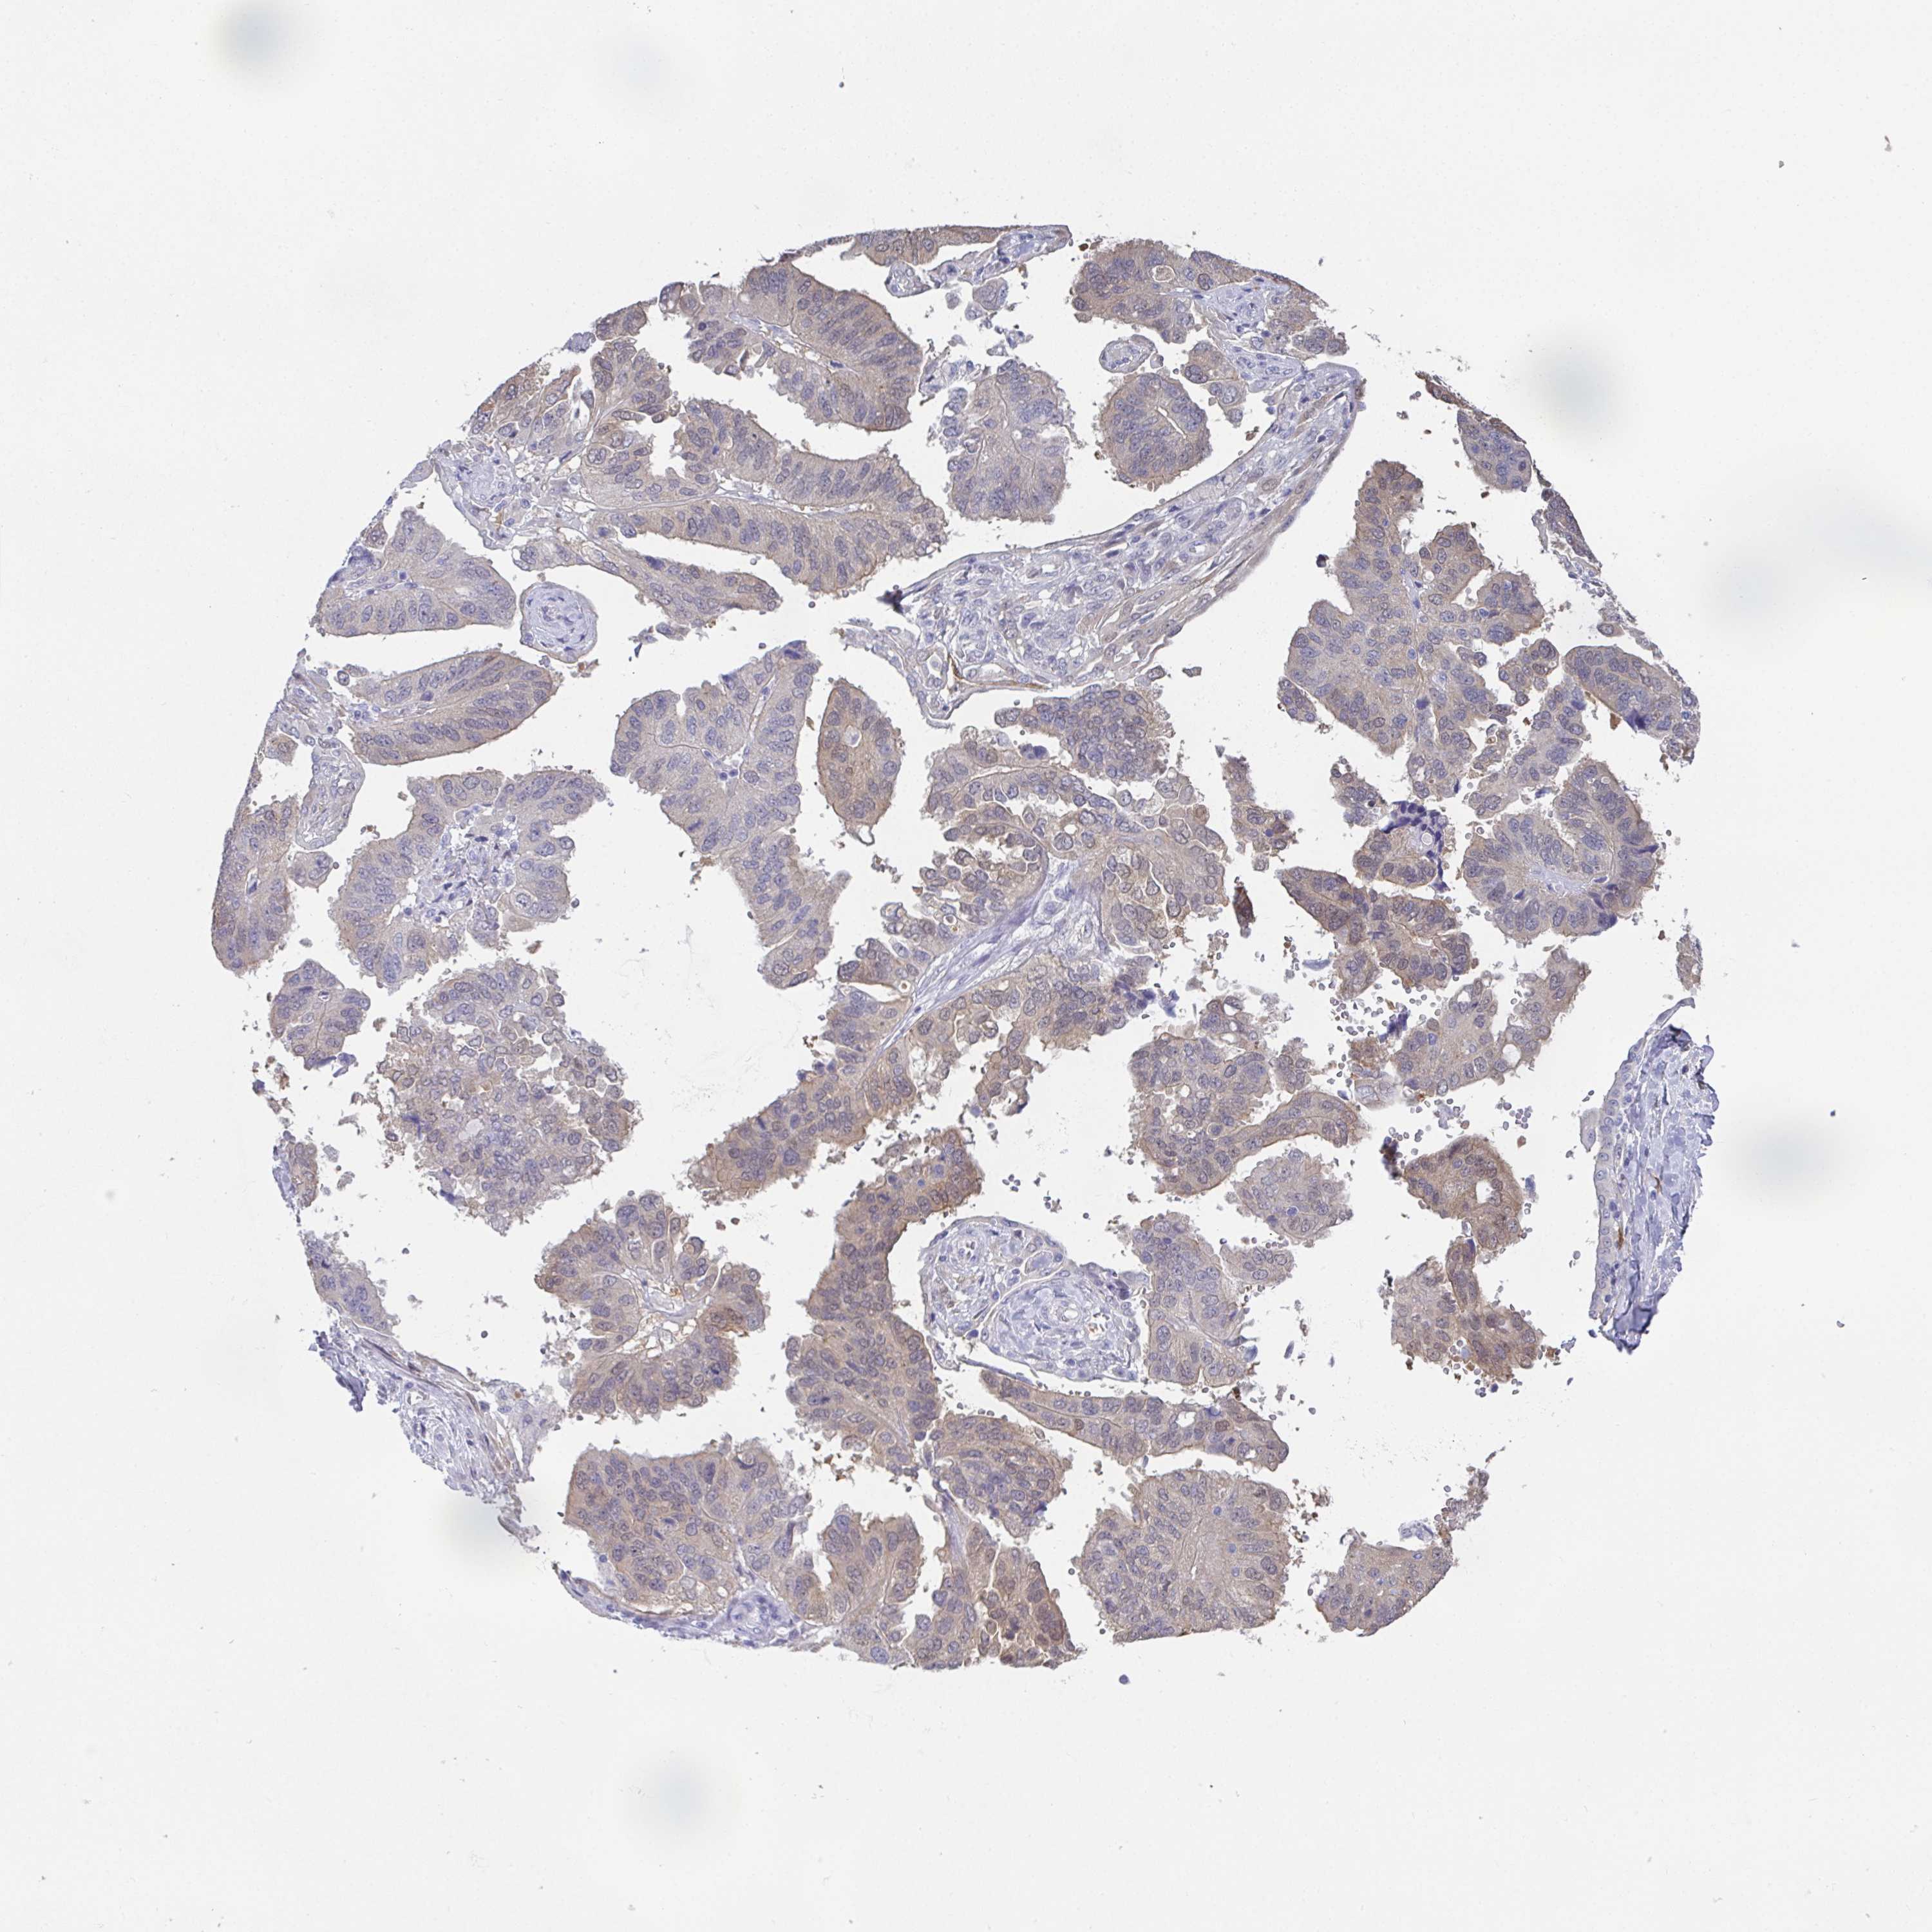

OVARIAN CANCER - Protein expressioni

A mouse-over function shows sample information and annotation data. Click on an image to view it in a full screen mode. Samples can be filtered based on level of antibody staining by selecting one or several of the following categories: high, medium, low and not detected. The assay and annotation is described here.

Note that samples used for immunohistochemistry by the Human Protein Atlas do not correspond to samples in the TCGA dataset.

Antibody stainingi

Antibody staining in the annotated cell types in the current human tissue is reported as not detected, low, medium, or high, based on conventional immunohistochemistry profiling in selected tissues. This score is based on the combination of the staining intensity and fraction of stained cells.

Each image is clickable and will lead to virtual microscopy that enables deeper exploration of all samples and also displays staining intensity scores, fraction scores and subcellular localization as well as patient and tissue information for each sample.

Antibody HPA007338

Antibody CAB018603

Antibody CAB019276

Staining

High

Medium

Low

Not detected

Cystadenocarcinoma, serous, NOS

Cystadenocarcinoma, mucinous, NOS

Carcinoma, endometroid

Carcinoma, NOS